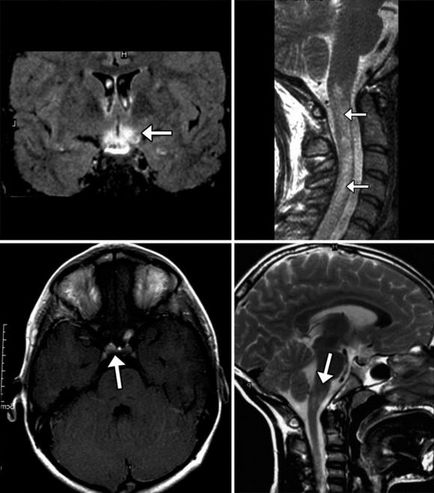

Cel puțin până de curând, a fost studiat în creierul uman. Apariția de tehnici, cum ar fi tomografie computerizata si imagistica prin rezonanta magnetica a permis în mod fiabil detecta modificări patologice nu numai creierul, ci și întregul cap, inclusiv oasele scheletului facial, fără nici un pericol pentru organism. Necesitatea unei astfel de proceduri stabilite de către medicul curant. Motivul poate fi următorii factori:

- leziuni traumatice cerebrale, traumatisme acute scheletului facial;

- plângeri frecvente de amețeală, apar fără nici un motiv aparent, dureri de cap;

- necoordonare;

- inflamație a sinusurilor paranazale, regiunea facială a craniului;

- umflarea feței, gâtului, cap, umflarea ganglionilor limfatici;

- Condițiile convulsivante (în special, mușchii feței);

- polipi, proliferarea mucoasei nazale și a gâtului.

Cand este administrat CT craniu

Studiul relevă stadiile timpurii ale efectelor traumei, a proceselor tumorale in oasele regiunii faciale, boli infecțioase, reprezintă un pericol considerabil pentru pacient, deoarece acestea se pot răspândi la creier. Un studiu, de asemenea, corpuri străine, a se vedea canalul plăgii și chiar sângerare ușoară și spațiul de acumulare de puroi, hematom.